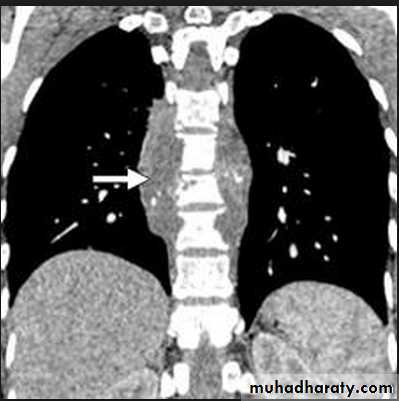

Massive pleural effusion with mediastinal shift to the left.

(A) Chest radiograph

(B) CT coronal reconstruction. A massive effusion displaces the mediastinum to the left. CT shows the important pleural effusion together with the enhanced atelectatic left lung.

Note also the depression of the right hemidiaphragm (arrows).